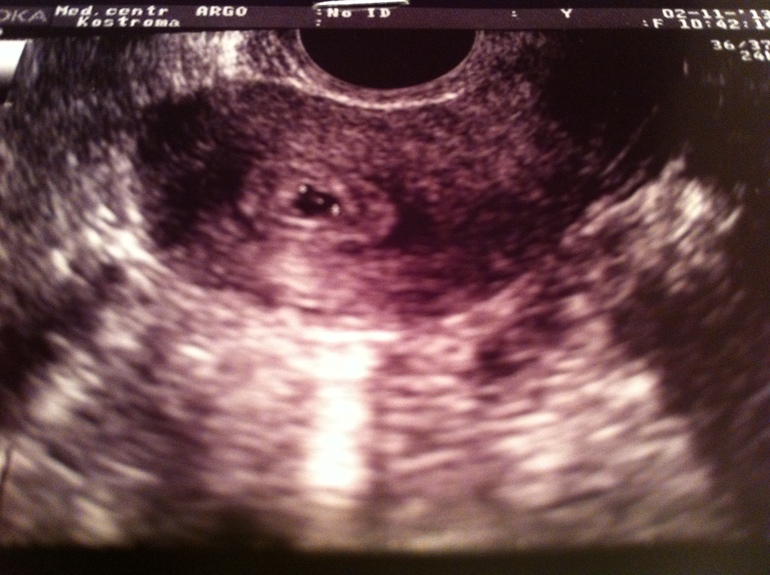

Возвращение Даши или как я забеременела!